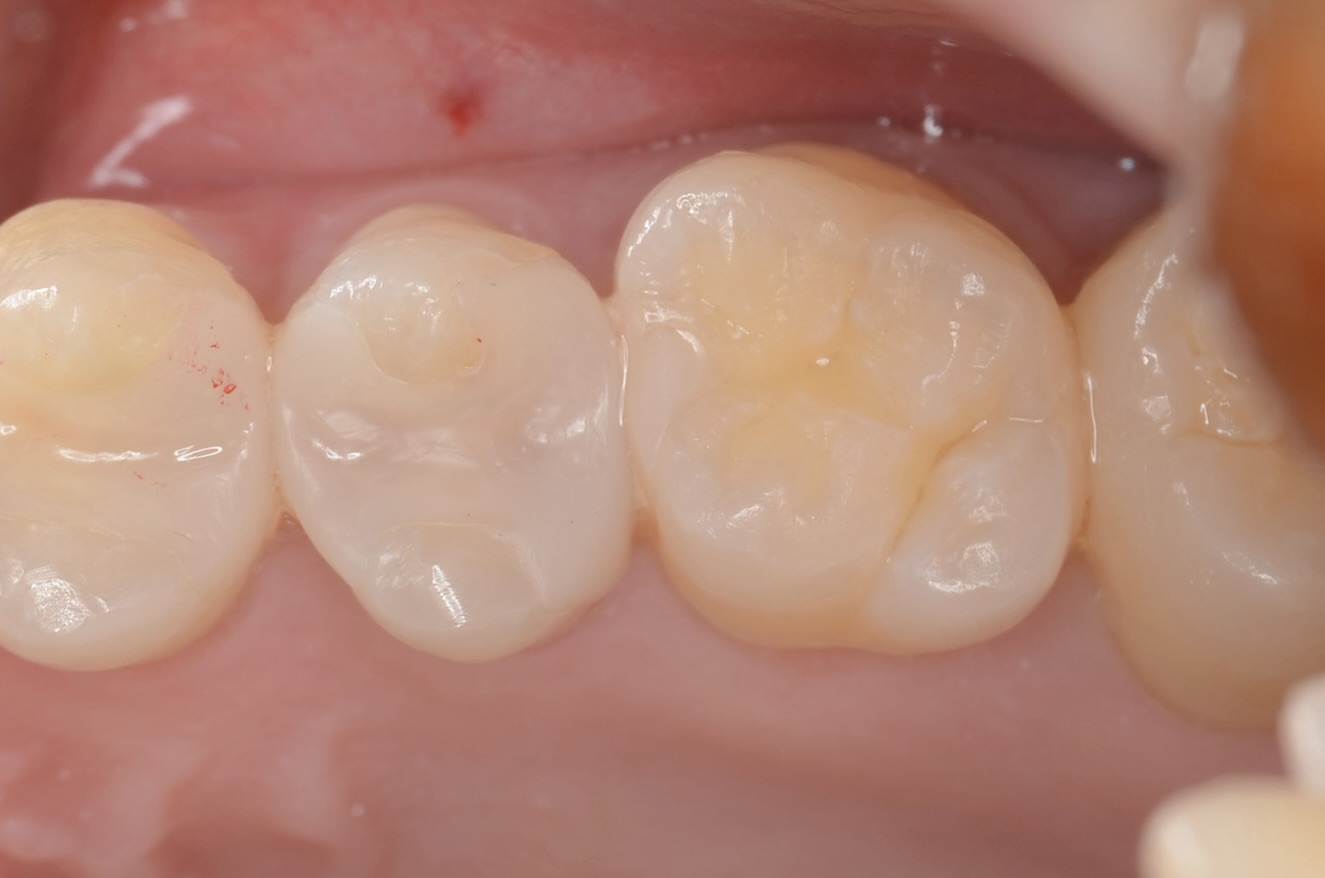

After

1週間後

広がった歯間が自然に閉じています。